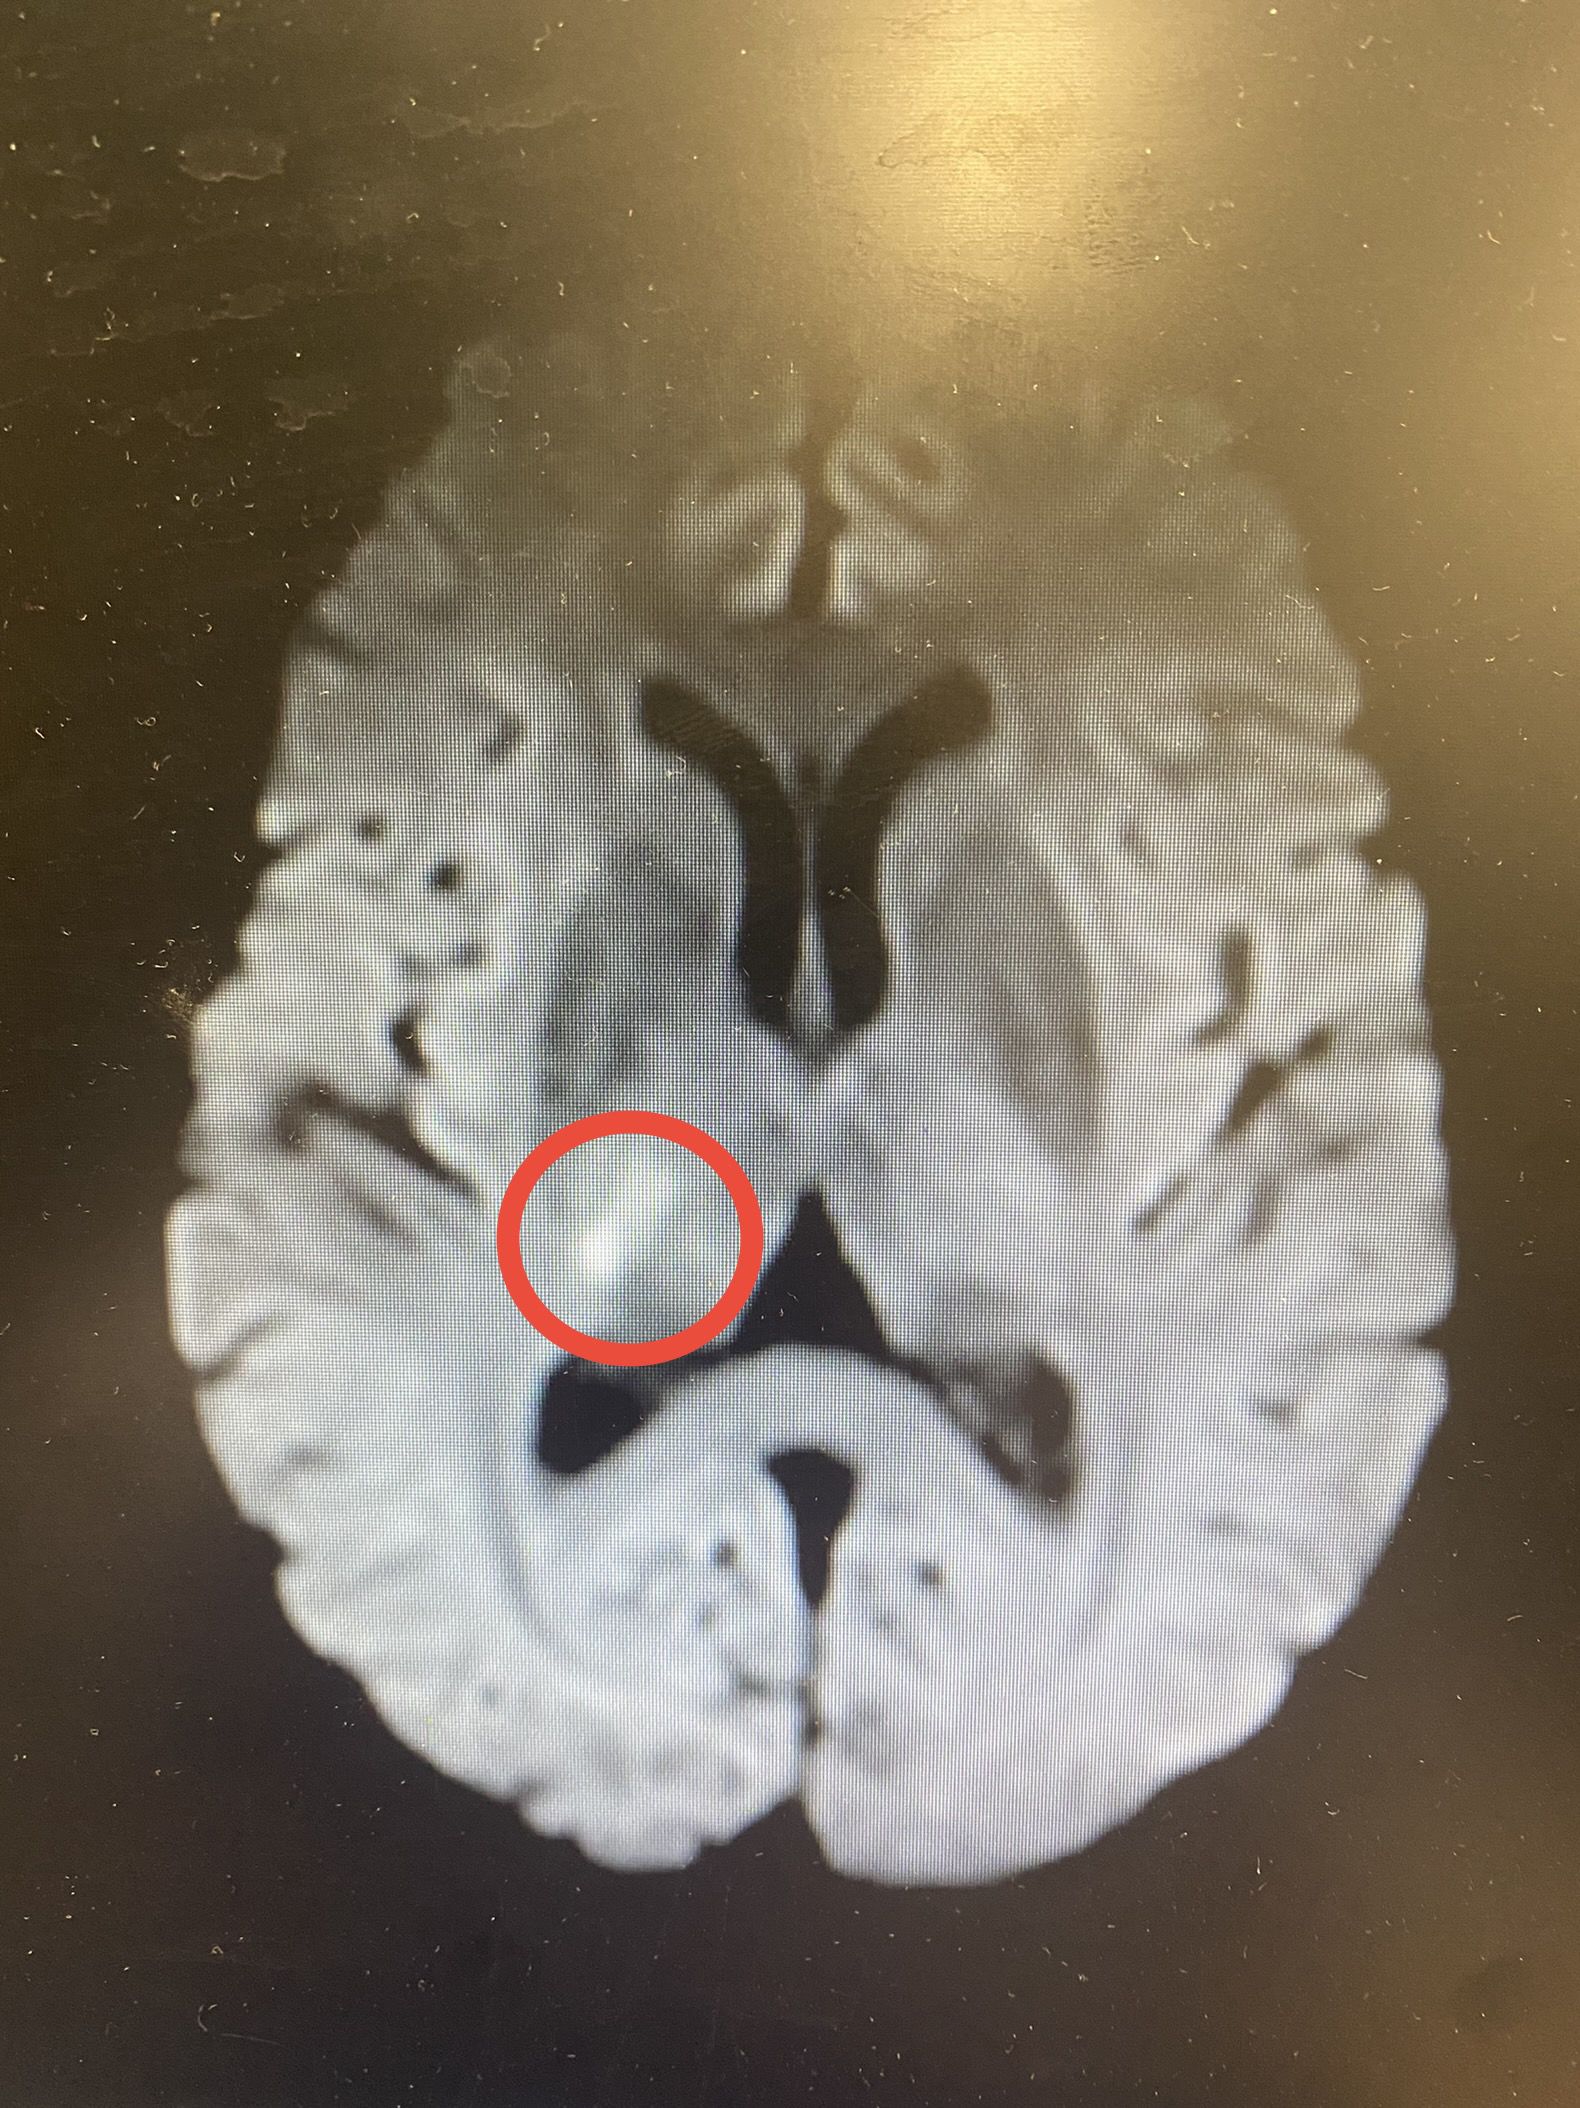

患者王某,女,66岁。因“突发左侧肢体麻木伴左侧忽视6小时”主诉入院,查体:神志清,左侧肢体痛觉减退,左侧肢体认识不能。NIHISS评分:3分。急诊头颅核磁共振DWI序列提示:右侧丘脑新发梗死灶(图1),MRA提示右侧大脑后动脉闭塞(图2)。

图1:右侧丘脑新发梗死灶